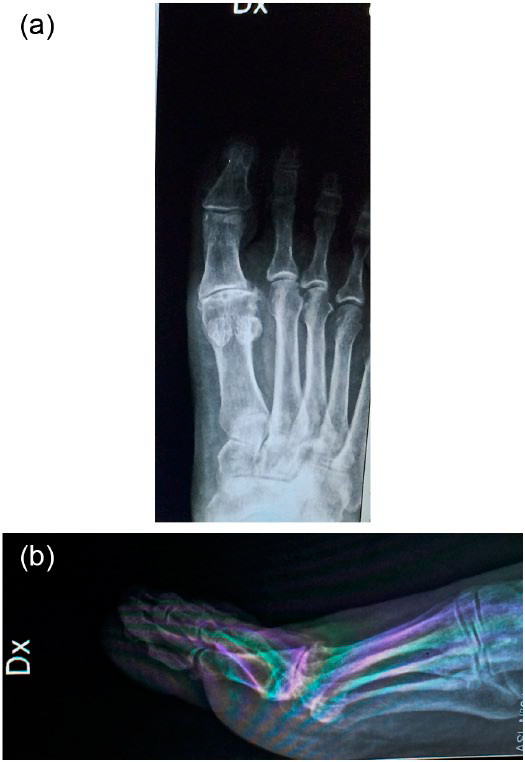

Pre-operatorio con notevole artrosi della prima articolazione metatarso-falangea